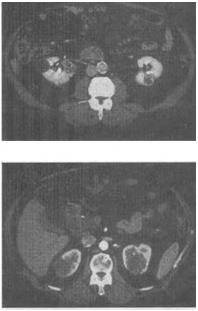

男,54岁,无痛性血尿1个月余,根据所示图像,最可能的诊断是()。

A、多发性肾囊肿

B、多囊肾

C、左侧肾癌并右肾转移

D、右侧肾囊肿合并左侧肾癌

E、多发性肾癌并双肾囊肿

E